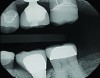

Thanks to the digitization of the final abutment, a monolithic e.max restoration was designed, milled, and ready for delivery prior to the office receiving the custom abutment. Upon delivery, the provisional restoration and solid abutment were removed. The new custom abutment was tried-in, along with the new e.max restoration to verify fit and occlusion. After the restoration was conditioned with Monobond Etch & Prime (Ivoclar Vivadent), the abutment was torqued to 35 Ncm, Teflon tape was placed in the screw access, and the restoration was cemented with SpeedCem (Ivoclar Vivadent) (Figure 5). Equigingival margin placement generated by the custom abutment design ensured thorough removal of excess cement. A post-operative radiograph was taken (Figure 6).

Fig 6. Post-operative radiograph.

Figure 6